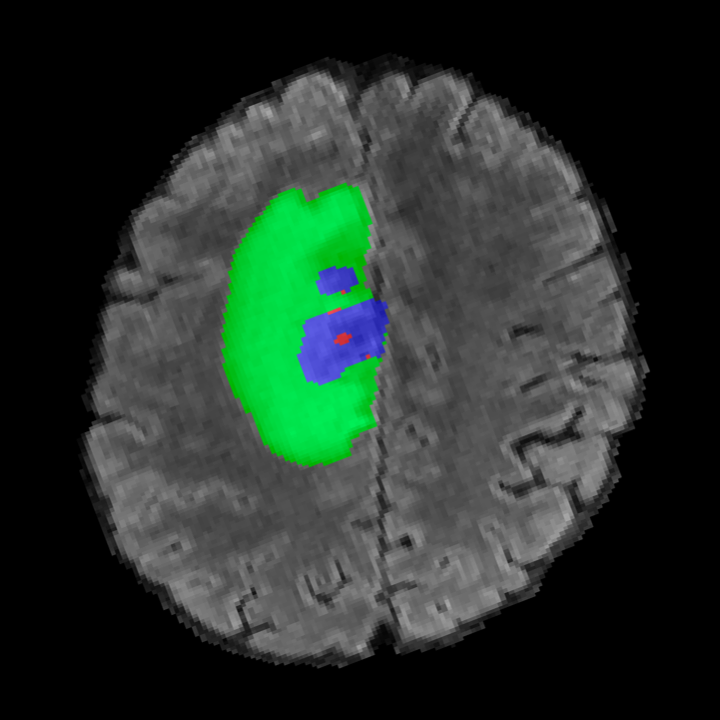

Tumour Information Preservation. For the brain tumor segmentation, we use a Swin UNETR model[28, 70], trained with random rotation, and intensity as data augmentation. On the test set with human ground-truth annotations (), the brain volumes generated from single slice input preserve the volume of the different tumour components (paired t-test, for all 3 classes). In Figure 4, we highlight the tumor profiles of the generated MRIs compared to the ground truth tumour profile. The real MRI Dice score in the test set is 85.15 while the generated MRIs from a single slice have a dice score of 83.09. This shows how the generated MRIs indeed preserve the tumor information and can act as an affordable and informative pseudo-MRI, before conducting an actual costly MRI examination in hospitals. More detailed results are provided in supplementary material.

Leveraging Context. Since we train on a predominantly cancerous brain dataset, one question that might arise is whether X-Diffusion generated MRIs preserve tumour information when the given inputs do not intersect with any tumour. We perform experiments varying the input slice index used to generate the 3D brain MRIs and measure the performance for input slices with no intersection with the tumour (not a single pixel with tumor label in the input slice). We also measure performance when only input slices are selected from tumor range. The Dice Scores of the random slices, no-tumour, and only-tumour are 83.09, 79.23, and 83.68 respectively. As can be seen here, the brain volumes generated from input slices with no tumour still preserve tumour information in reconstructed brain volumes despite a small drop in performance. This indicates that X-Diffusion is leveraging the context to preserve key information, such as tumor locations. This observation is consistent with how tumor segmentation models with global context [13] perform better than local-based U-Nets. More details are provided in supplementary material.